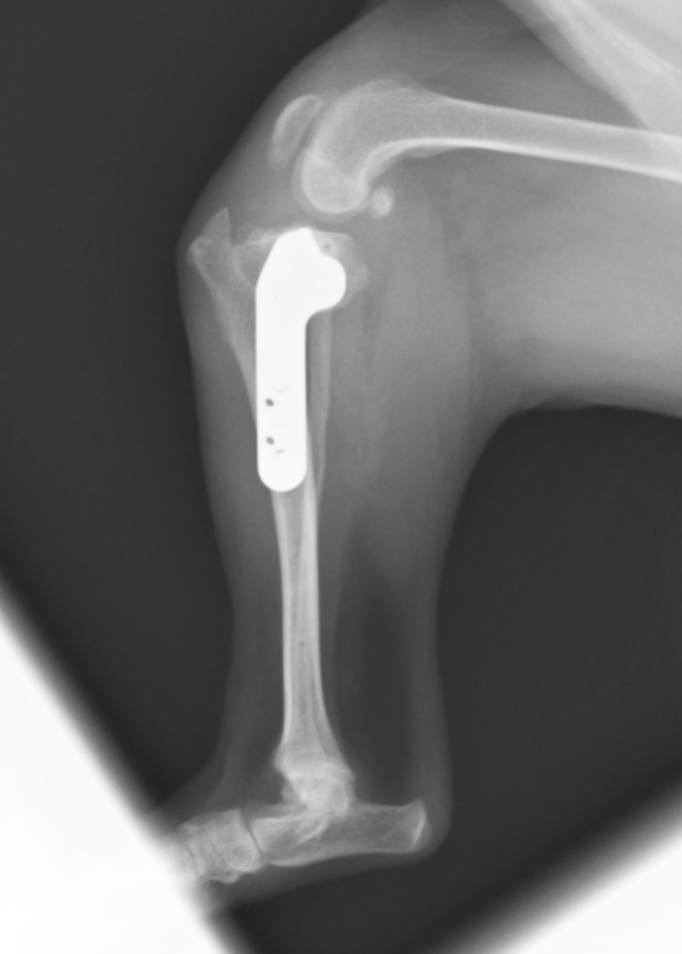

TPLOの術後のレントゲンです。約7度になっており、計画通りに手術が行えています。脛骨のずれ(CrTT)も消失しているのがわかると思います。 このように、円形に切ることで、膝の回転中心をずらすことなく骨を矯正できるため、骨短長がほとんどなく(長さが変わりません)、荷重のズレを少なくすることができます。

フレンチブルドッグの症例です。TPAが高く回転距離が長くなっています。TPAが高い症例はTPLOの合併症が起きやすたいめ、その手術計画は注意して行う必要があります。